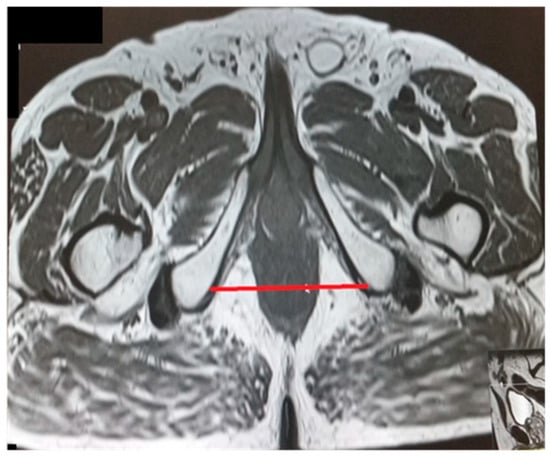

The pelvic measurements on MRI (Figure 2, Figure 3, Figure 4, Figure 5, Figure 6 and Figure 7) were carried out by the author, and to maintain the reproducibility of the results, measurements were taken, whenever possible, at the same anatomical levels.

Figure 5.

Intertuberous distance.